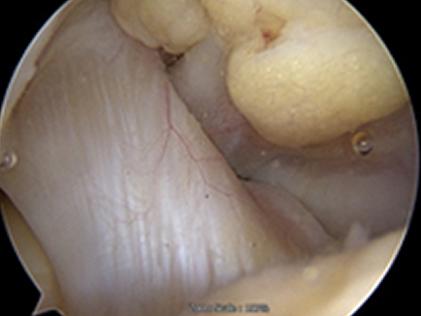

자가골수줄기세포치료는 국소 마취 후 바늘을 이용해 자신의 골수에서 줄기세포를 채취하는 방식입니다. 원심분리기를 통해 줄기세포를 분리 농축하는데 이 때 줄기세포는 8~9억개의 재생세포로 분화됩니다. 손상된 무릎을 관절 내시경으로 보면서 주사로 줄기세포를 주입하면 시술은 종료됩니다.

치료 전 붉게 패여 손상된 연골이 치료 후 정상적으로 회복된 모습

before img after img